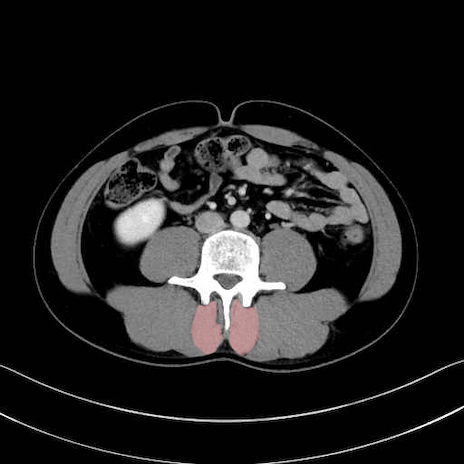

多裂筋 (Multifidus)